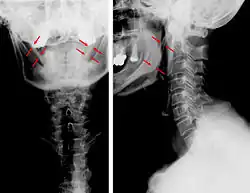

Anteroposterior and lateral radiographs of cervical spine showing ossification of the stylohyoid ligament on both sides

Imaging is important and is diagnostic. Visualizing the styloid process on a CT scan with 3D reconstruction is the suggested imaging technique.[13] The enlarged styloid may be visible on an orthopantogram or a lateral soft tissue X ray of the neck.